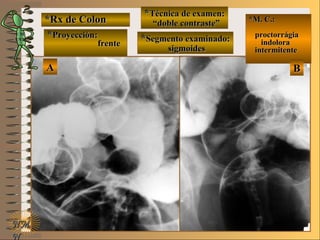

*Rx de Estómago*Rx de Estómago

**Proyección:Proyección:

**Técnica de examen:Técnica de examen:

A-A-

B-B-

C-C-